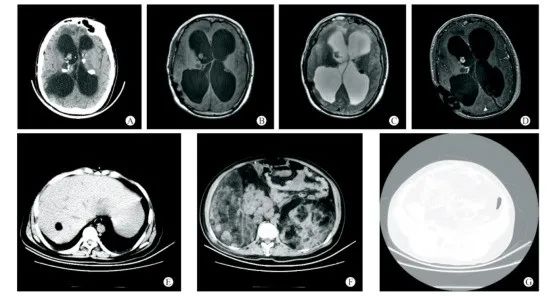

图6 19岁女性结节性硬化症患者的头颅CT+MRI平扫影像[6]

患者临床表现为癫痫及精神发育异常,右面部色素沉积斑、四肢及躯干多发色素脱失斑、双侧峡部皮脂腺瘤,胸椎多发斑片状致密影。A-C:头颅CT+MRI平扫示双侧室管膜下及皮层下多发结节样钙化灶;D:T2FLAIR示大脑半球皮层及皮层下多发异常高信号影。

图7 19岁男性结节性硬化症患者的CT影像[6]

患者有癫痫并发育迟缓,9年前有双侧侧脑室室管膜瘤切除史。A-D:双侧室管膜下多发结节样钙化灶,右侧侧脑室内软组织结节;E:肝内错构瘤;F:双肾巨大错构瘤;G:椎体及双侧髂骨多发骨质硬化。